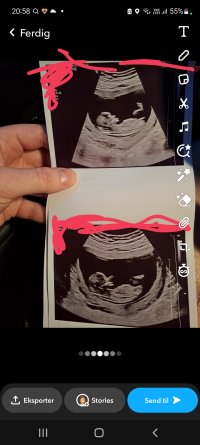

Gjette kjønn ? Nub teori

Kan fortsatt reise seg opp tror jeg, men på det bilde ser den lang og flat ut som ei jente

Ser ut som en jente, men fortsatt tidlig så det er ikke helt sikkert før nærmere 12+5, men jeg tror det er stor sjanse for at det vil forbli en jenteEr 12+3 i dag. Hvilket kjønn tror dere det er ?

Hjertelyden var på 161

Synes dette ser mer jente enn gutt ut. Nub er litt lang til å være gutt. Noen jenter kan han litt vinkel på nub i starten før den legger seg helt flatt. Oppdater når du har vært på ny ultralyd daEr 12+3 i dag. Hvilket kjønn tror dere det er ?

Hjertelyden var på 161

Yep, dette er en jente13+0

Dette er ei jente. Gratulerer13+0

Helt sikker ?Yep, dette er en jente